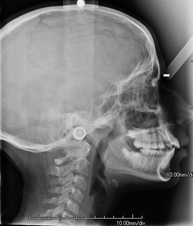

- RX Cráneo

Técnica mediante la cual, utilizando rayos X, se obtienen imágenes del cráneo para su estudio. Indicaciones: traumatismo, cierre precoz de suturas craneales.

- RX Columna cervical

Técnica mediante la cual, utilizando rayos X, se obtienen imágenes de la columna cervical para su estudio. Indicaciones: traumatismo, contractura cervical, dolor articular.

Técnica mediante la cual, utilizando rayos X, se obtienen imágenes de la columna cervical para su estudio. Indicaciones: traumatismo, dolor cervical.